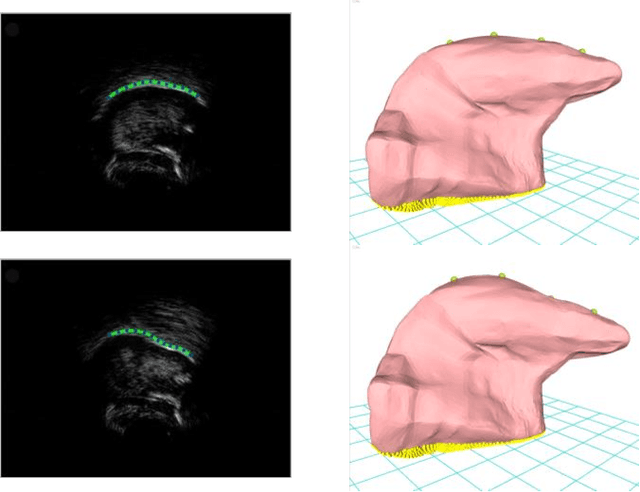

Abstract:This article describes a contour-based 3D tongue deformation visualization framework using B-mode ultrasound image sequences. A robust, automatic tracking algorithm characterizes tongue motion via a contour, which is then used to drive a generic 3D Finite Element Model (FEM). A novel contour-based 3D dynamic modeling method is presented. Modal reduction and modal warping techniques are applied to model the deformation of the tongue physically and efficiently. This work can be helpful in a variety of fields, such as speech production, silent speech recognition, articulation training, speech disorder study, etc.